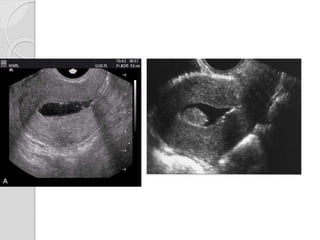

Ultrasound

Sonographic features are variable.

Ultrasound Sonographic features arevariable.  Normal appearing uterus  Focal or diffuse myometrial bulkiness, typically of the posterior wall  Thickening of the transition zone  Subendometrial echogenic linear striations  Subendometrial echogenic nodules  Small myometrial cysts / sub endometrial cysts  Heterogeneous myometrial echotexture

• #42 This transabdominal ultrasound image shows a large (bulky) uterus with a diffusely infiltrative, in homogenous appearance of the myometrium with dirty, streaky shadowing posteriorly. The uterus shows a globular shape with the endometrium almost obscured. These features are  typically seen in adenomyosis. However, both fibroids/ leiomyoma of the uterus can simultaneously be present with diffuse adenomyosis as in this case

• #44 Transvaginal scan showing asymmetric thickness of the myometrium with tiny subendometrial cysts representing ectopic endometrial glands (Adenomyosis)

• #55 US and MR images demonstrate adenomyosis